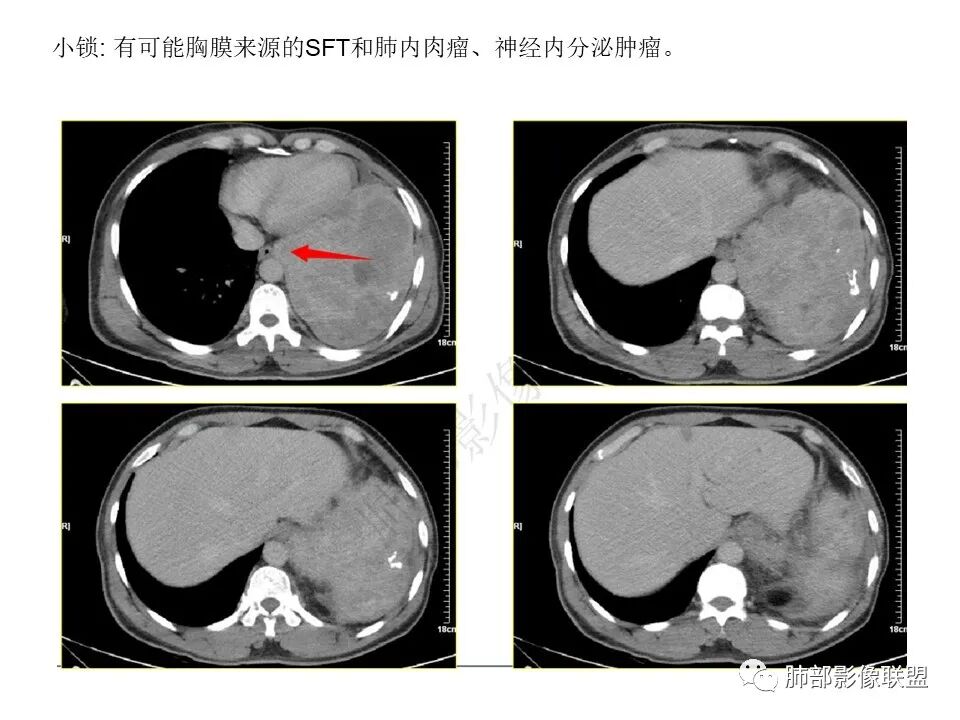

还是支持脏层胸膜来源SFT首选,其次肺内肉瘤

因为:

1局部胸膜起源,所以与胸膜分界不清

2、肺内病变,局部胸膜侵犯

如果胸膜侵犯,局限在这里,而且支气管侵犯不是很明显,似乎不合理

内部坏死都可以,钙化,SFT几率高一些

琦遇:

支持南大!感觉恶性程度偏低,这么巨大肉瘤,恶性SFT

孤立性纤维性肿瘤(SFT)